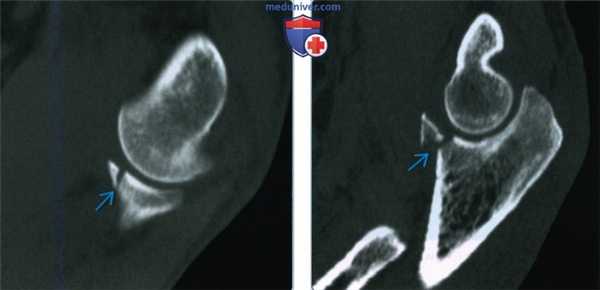

(Справа) На сагиттальной КТ с реформатированием у пациента, которому проведена пластика шурупами головки лучевой кости и мыщелка плечевой кости, можно видеть выступание шурупа головки лучевой кости в проксимальный лучезапястный сустав. Пациент жаловался на боль при супинации/пронации. (Слева) На сагиттальной КТ с реформатированием у пациента, рентгенограммы которого интерпретировали как нормальные после травмы локтевого сустава, определяется незначительно смещение переднего кортикального слоя головки лучевой кости.

(Справа) На фронтальной КТ с реформатированием у этого же пациента визуализируется линия перелома, проходящая через шейку лучевой кости. Этот перелом невозможно было выявить даже при тщательном анализе рентгенограмм. Несмотря на то, что КТ известна как лучший метод выявления и характеристики переломов головки лучевой кости, иногда удается выявить переломы шейки лучевой кости. (Слева) Этот пациент с болью в локтевом суставе получил травму, однако на рентгенограммах (не показаны) перелом не определялся. На фронтальной МРТ Т2ВИ FS определяется отек костного мозга в головке лучевой кости. В этом случае пациенту необходимо лечение по поводу перелома шейки лучевой кости без смещения.